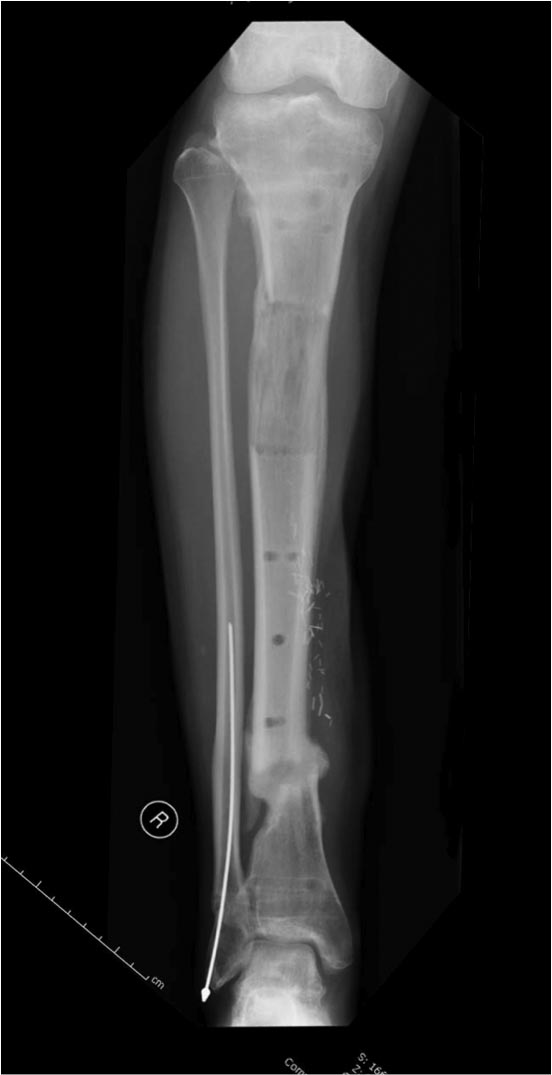

Данный случай не огнестрельная рана, а результат мотоциклетной аварии.

Независимо от повреждения при таких обширных дефектах мягких и костной

тканей применяется схожая тактика. Как видно, после нескольких I&D для

создания “pseudo membrane” применили цилиндрический блок из цемента.

Дефект мягких тканей закрыли свободным Anterior Thigh Graft. Из малого

доступа цилиндр удален небольшими кусочками, а пространство заполнили

бусами для освобождения пространства. По мере приближения регенерата

освободили пространство удалением бус через небольшой разрез. Этап

созревание регенерата можно было ускорить усилением интрамедуллярным

гвоздем, но решили закончить методом Илизарова.